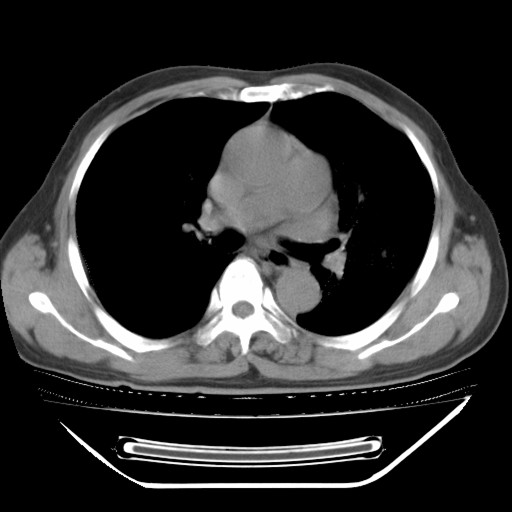

以下是引用hhcckk在2009-5-29 10:34:00的发言:[br]左下肺片絮状边缘模糊影,考虑感染,建议治疗后复查[br]